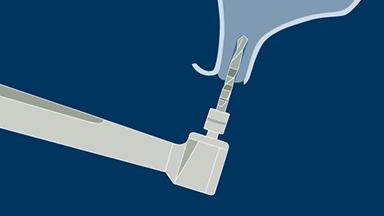

A osteotomia do implante é uma etapa cirúrgica essencial na implantodontia. Termina com a inserção de um implante dentário que posteriormente fornecerá ao paciente um substituto fixo ou removível para a ausência de dentes. Neste módulo, descreveremos primeiro a técnica correta de preparação óssea para a instalação do implante. Posteriormente, abordaremos os ajustes do protocolo necessários em diferentes densidades ósseas. Finalmente, discutiremos os riscos potenciais associados à técnicas inadequadas de osteotomia.

- definir a sequência, velocidade e técnica de perfuração e reconhecer sua relação com a estabilidade primária do implante e a osseointegração

- selecionar o procedimento de perfuração apropriado para determinados tipos ósseos